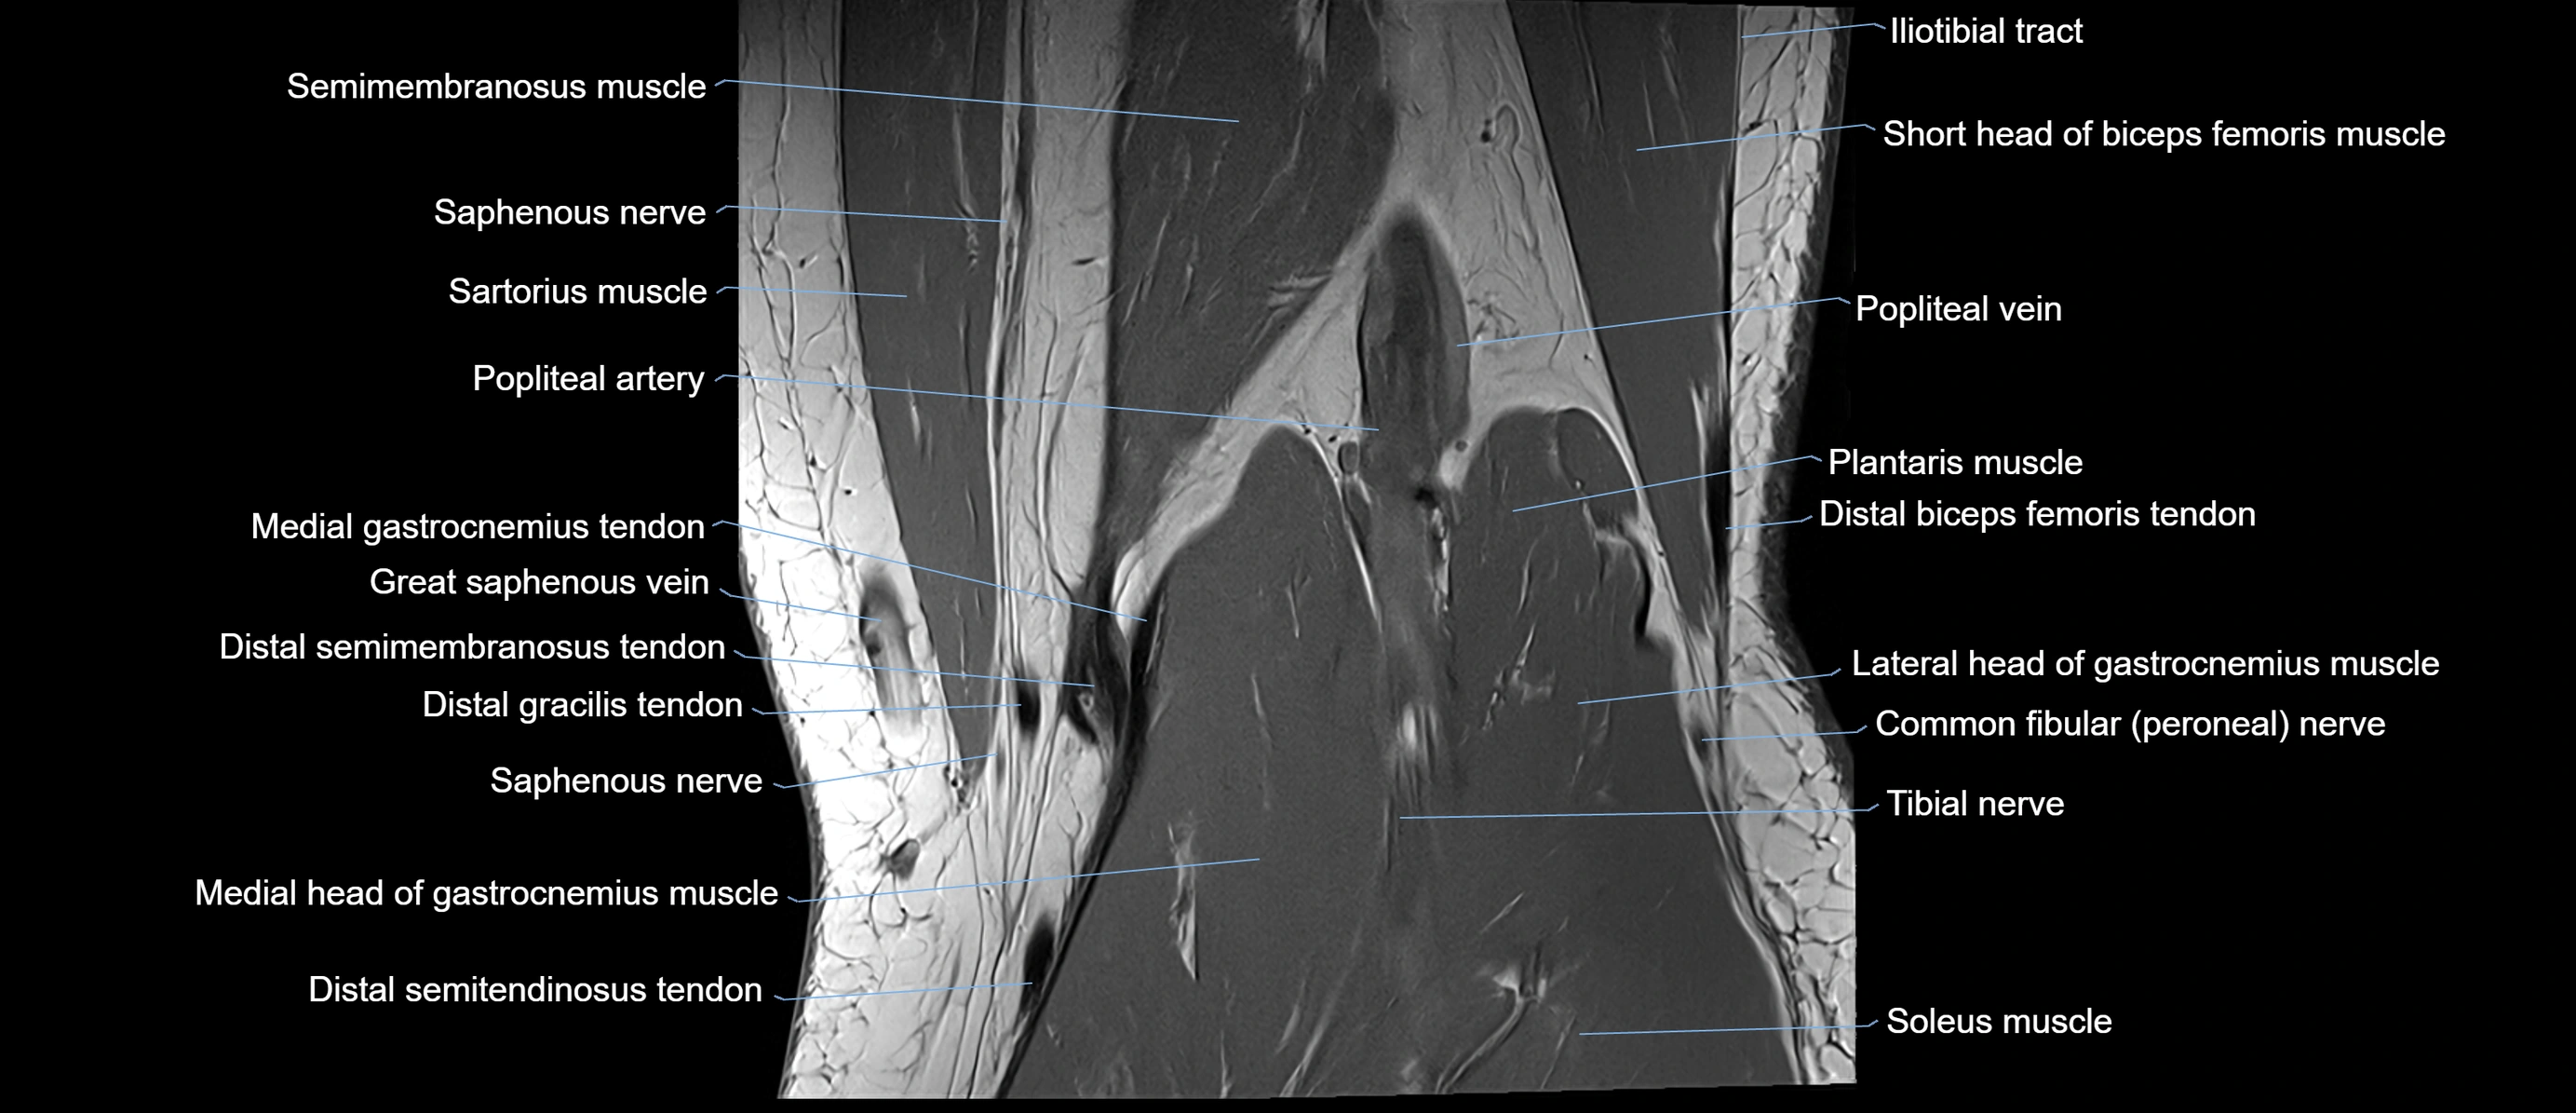

- Biceps femoris muscle (Long head)

- Biceps femoris muscle (Short head)

- Common fibular nerve

- Distal biceps femoris tendon

- Distal semimembranosus tendon

- Distal semitendinosus tendon

- Gastrocnemius muscle

- Gracilis tendon (Distal)

- Lateral head of gastrocnemius muscle

- Medial gastrocnemius tendon

- Medial head of gastrocnemius muscle

- Medial sural cutaneous nerve

- Muscular branches of tibial nerve

- Plantaris muscle

- Popliteal artery

- Popliteal lymph nodes

- Popliteal vein

- Popliteus muscle

- Saphenous nerve

- Sartorius muscle

- Semimembranosus muscle

- Semitendinosus muscle

- Soleus muscle

- Tibial nerve